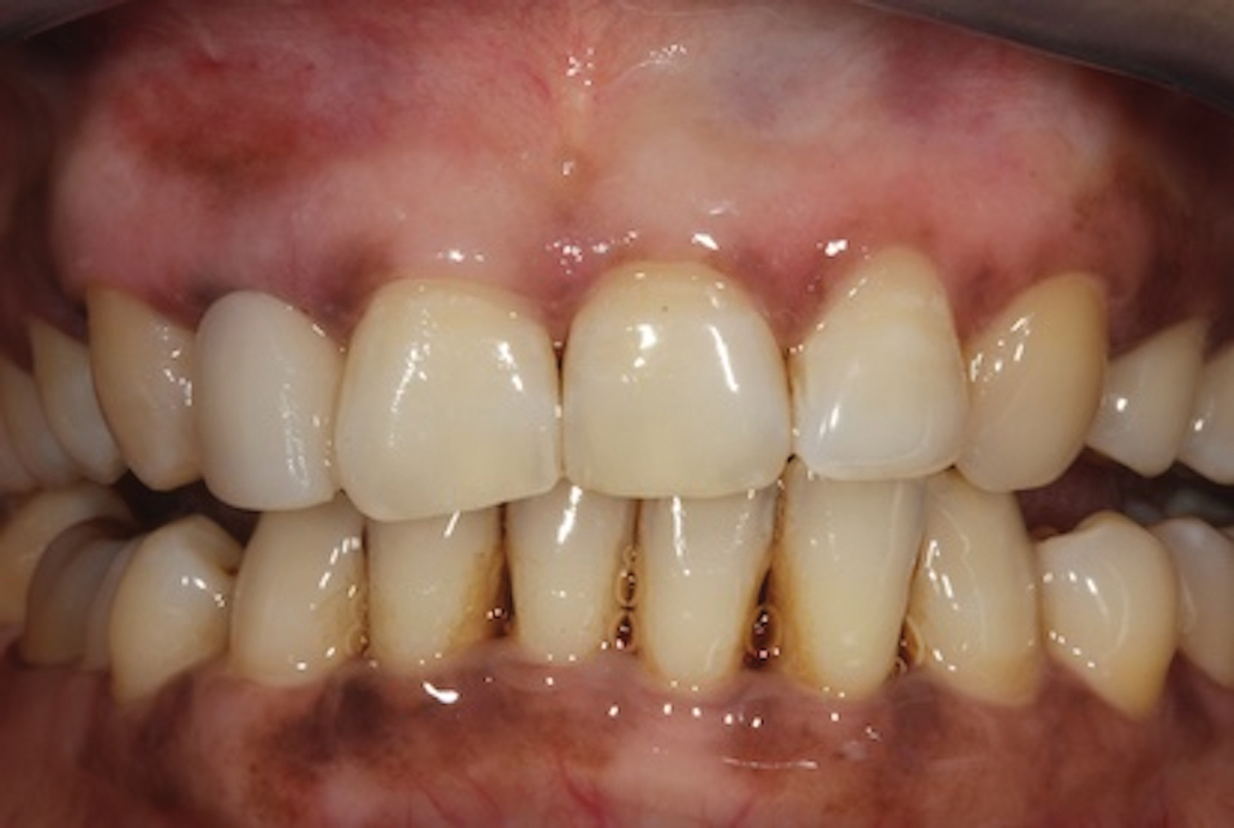

Depending on whether patients present with an existing edentulous space or a non-restorable tooth requiring extraction, as well as other factors, their long-term treatment goals may vary. Nonetheless, each case should be evaluated to identify patients' needs regarding immediate restoration. In the example case presented here, a radiographic examination of a discolored canine lead to the discovery of a lateral incisor (tooth No. 7) with internal resorption that required extraction (Figure 1). The tooth was extracted, and an implant was subsequently placed (Figure 2); however, the patient would be unable to complete the treatment for an extended period of time, so a fiber-reinforced composite bridge was chosen to serve as an ideal long-term provisional replacement option.

(1.) Pretreatment radiograph of tooth No. 7 showing an internal resorption lesion.

Figure 1